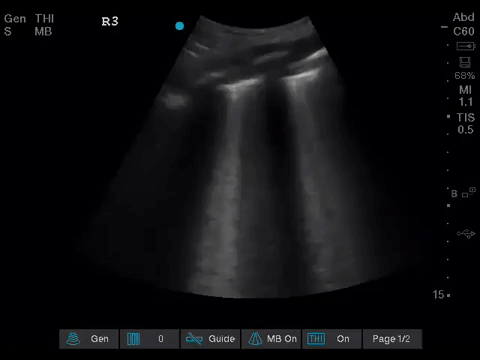

The POCUS team was asked to specifically to assess her lungs to help determine the cause of her dramatically increased oxygen requirements.

Before giving their clinical interpretation of the LUS findings, the POCUS team also scanned the heart and vasculature to obtain a more complete picture.

1. When scanning the lungs, a comprehensive, bilateral lung scan is far superior to a single clip; as this will offer more information and permit an interpretation based on the overall pattern of findings. Had this patient only had the R1 area scanned, for example, we may have reached the erroneous conclusion that her hypoxemia was likely due to pulmonary edema.